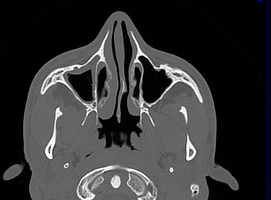

Лицевой череп состоит из крупных костей (верхняя и нижняя челюсти, лобные кости, скуловые кости) и сгруппированных вокруг них остальных мелких костей. При травмах лицевых костей часто наблюдается смещение мелких отломков, которые не видны при обычной рентгенографии. Мультиспиральная компьютерная томография позволяет детально изучить кости лицевого черепа, а также углубления, которые являются вместилищем для важных органов (глазницы, полость носа, ротовая полость).

Метод КТ основан на применении рентгеновского излучения и различной способности тканей поглощать рентгеновские лучи. Костные структуры обладают наибольшей плотностью по сравнению с другими тканями, поэтому в большей степени поглощают рентгеновские лучи и лучше всего визуализируются при данном исследовании.

КТ костей лица является наиболее информативным методом диагностики травм лицевого черепа, посттравматических деформаций, аномалий развития, инородных предметов в носовой полости и околоносовых пазухах. Кроме того, мультиспиральная КТ применяется при воспалительных заболеваниях ЛОР-органов, а также для выявления опухолевых образований доброкачественного и злокачественного характера.

Детальные изображения костей лицевого черепа получаются за счет вращения трубки томографа с излучателями рентгеновских лучей вокруг объекта исследования. В аппаратах увеличено количество сверхчувствительных детекторов, позволяющих производить множество послойных снимков с толщиной среза от 0,5 мм, которые затем преобразуются в трехмерные пространственные модели черепа. Такие инновационные возможности аппаратов обеспечивают проведение точной и достоверной диагностики.